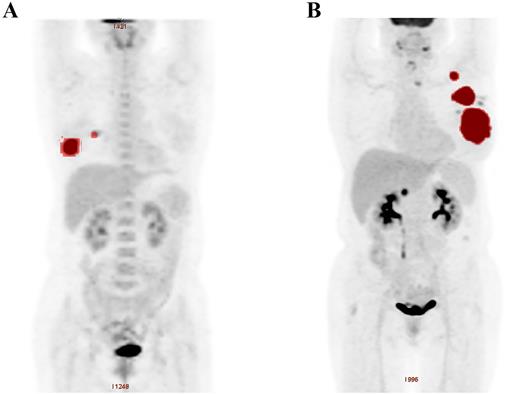

In the whole population, the median TMTV0 was 87 cm3 (range: 3-312 cm3). The ROC analysis showed that the optimal TMTV cut-off value for estimating PFS and OS was 90 cm3. The areas under the curves (AUCs) were 0.767 for PFS and 0.719 for OS. The sensitivities and specificities were 73.6% and 77.2% for PFS, and 71.3% and 73.2% for OS respectively. The prognosis of patients with high TMTV0 (TMVT0 > 90 cm3, n = 44) was significantly worse, with 5-year PFS and OS of 44.5% and 62.3%, respectively, while those with low TMTV0 (TMVT0 ≤ 90 cm3, n = 50) were 74.8% and 84.9% (P = .005 for PFS and P = .017 for OS). In multivariate analysis, TMTV0 also remained a more reliable predictor of survival than other prognostic factors including TLG (TMTV0: P < .001 for PFS and OS; TLG: P = .003 and P = .002 for PFS and OS individually). In this study, we also demonstrated that baseline high serum β2-microglobulin level and ECOG performance status predicted both shorter PFS and shorter OS.

We then constructed a new prognostic model of PBL based on serum β2-microglobulin level, ECOG performance status in combination with TMTV0. According to whether there are adverse factors, we divide patients into four risk categories. The prognosis of the four groups was significantly different, with 5-year PFS of 86.9%, 62.5%, 38.6 and 19.3% (P = .001) and 5-year OS of 92.4%, 70.6%, 52.1% and 29.4 (P = .013), respectively.